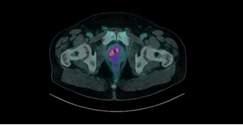

Figure 1.

18-F PSMA PET/CT in man with mixed prostate cancer (ductal plus acinar PCa Grade Group 4/Gleason score 8): intraprostatic standardized uptake value (SUVmax) was equal to 4 9 (a) in the absence of distant metastases (b)

Two Caucasian men 58 and 62 years old were admitted to our Department for dysuria: the patients had not familiarity for PCa and assumed antihypertensive drugs PSA values were equal to 5 6 and 2 8 ng/ml, digital rectal examination was highly suspicious for PCa and magnetic resonance image (mpMRI) showed for both the presence of a index lesion Prostate Imaging Reporting and Data System (PIRADS) score 5 The patients underwent extended transperineal prostate biopsy (18 cores) combined with four mpMRI/TRUS fusion biopsy using a 18 gauge needle under sedation and antibiotic prophylaxis (12, 13) The biopsy histology demonstrated the presence of a mixed PCa characterized by ductal and acinar PCa (Grade Group 4/Gleason score 8) with a Greatest Percentage of Cancer equal to 100%, a mean number of positive cores of 15 (3 targeted cores and 12 systematic biopsies)) and a mean total percentage of cancer equal to 45% (35-55%) The clinical staging performing lung and abdominal CT plus technetium-based bone scan did not demonstrate distant metastases and/or others primitive tumors; in addition, the 18-F PSMA PET/CT (5) showed in both patients an intraprostatic lesion provided of a standardized uptake value (SUVmax) equal to 4 6 and 4 9 in the absence of distant lesions suspicious for metastases (Figure 1) Following multidisciplinary evaluation, the patients underwent open radical prostatectomy (RP) plus extended pelvic lymphadenectomy Definitive specimen showed the presence in both cases of a mixed pT3bN1 PCa (ductal plus acinar Grade Group 4/Gleason score 8) with positive surgical margins, perineuronal invasion and nodes metastases (5/20 and 6/24, respectively) Postoperative PSA (one month from surgery) in the two patients was 0 8 and 0 3 ng/ml, therefore patients under-

Results: Conventional imaging was negative for distant metastases; 18F-PSMA PET/CT showed in both patients an intraprostatic lesion characterized by a standardized uptake value (SUVmax) equal to 4 6 and 4 9 in the absence of distant lesions suspicious for metastases Following multidisciplinary evaluation, the patients underwent radical prostatectomy plus extended pelvic lymphadenectomy Definitive specimen showed the presence in both cases of a mixed pT3bN1 PCa (ductal plus acinar pattern Grade Group 4) with positive surgical margins, neuronal invasion, and nodes metastases (5/20 and 6/24, respectively) Post-operative PSA in the two patients was 0 8 and 0 3 ng/ml, therefore patients underwent adjuvant therapy.